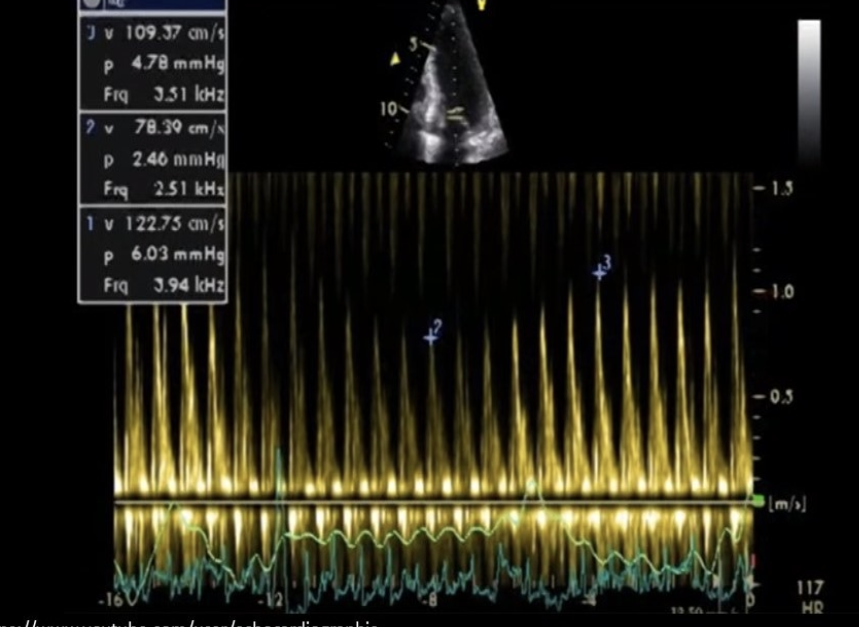

Dagger shaped waveform with high systolic velocity and late systolic peak reflects a dynamic obstruction

HOCM